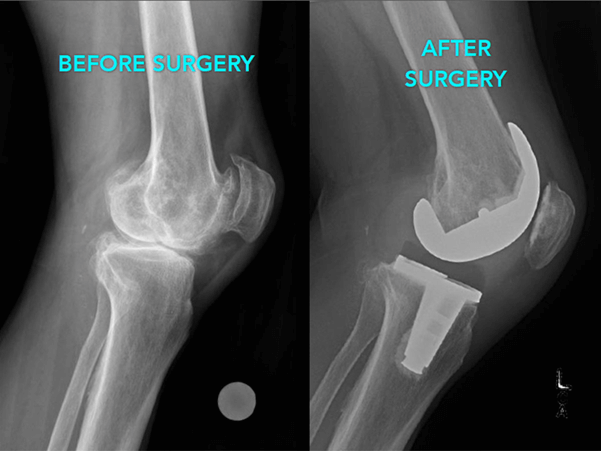

x rays of the affected joint (and other joints as well)to determine loss of joint space and to differentiate between OA and RA

What is Joint Replacement Surgery?

It is a method by which the surgeon removes the damaged cartilage and bone and replaces it with new metal and plastic joint surface to repair the connection and painless functioning of joints.